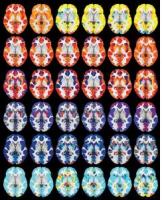

Pourquoi avons-nous le pas plus léger quand nous sommes heureux ? Cette équipe de neuroscientifiques de l’Université du Colorado à Boulder décrypte ce rôle central joué par ce neurotransmetteur associé à la récompense : en d’autres termes, la dopamine incite à agir plus vite pour satisfaire un désir et obtenir une récompense. Ces travaux, publiés dans la revue Science Advances va permettre de comprendre, voire de diagnostiquer et suivre, différentes affections médicales, comme la maladie de Parkinson et la dépression.

Quelles implications chez l’Homme ? Les personnes atteintes de la maladie de Parkinson perdent de nombreux neurones dopaminergiques dans leur cerveau. Elles éprouvent également de grandes difficultés à se déplacer. Pour explorer le lien entre la dopamine et le mouvement, les chercheurs ont demandé à des participants d'utiliser un joystick pour effectuer une série de mouvements vers l'une des 4 cibles situées à chaque coin d'un écran. Une cible offrait une récompense à chaque fois qu'elle était atteinte, tandis qu'une autre n'en offrait jamais. Les deux autres se situaient entre les deux. L’expérience révèle que :